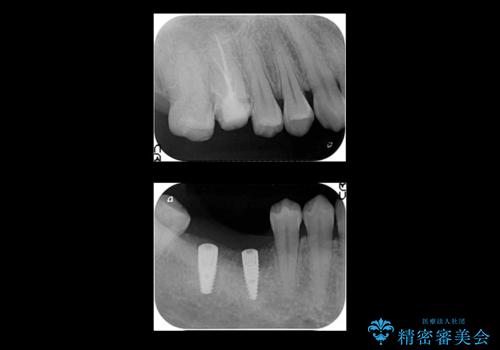

右下は虫歯がひどく、抜歯が必要でした。また、右下の一番奥の歯は親知らずのため使うことができない状態でした。

右上に部分矯正を行い、クリアランスを確保した後、右下にイプラントを2本埋入しています。

- およそ150万円 部分矯正30万円、インプラント治療37万円×2本、右上7emaxインレー、右上6 専門医による再根管治療およびジルコニアクラウン26万円費用は治療当時の料金となります